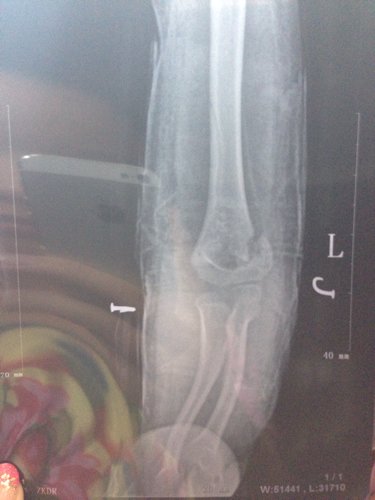

6岁宝宝肱骨髁上骨折,7月16日摔倒,手法复位成功,两周后拍片移位 请大家帮忙看看,这样移位会有影 6岁宝宝肱骨髁上骨折,7月16日摔倒,手法复位成功,两周后拍片移位。请大家帮忙看看,这样移位会有影响吗? 点击展开 hjf9418 2014-08-03 21:25 满意回答 完全合缝的很少。骨伤处愈合的骨它蒸掏结像焊接一样,很结实。只要没大影响(动敢件作活动)就行了。不要宝宝受二怪布次罪。 理知慧_1RbG 2014-08-03 21:42 宝宝知道提示您:回答为网友贡献,仅供参考。 相关问题 九月三十号,四岁半的儿子在幼儿园摔伤,导致右肱骨骨折,手动复位后移位,进行内固定手术,伤残鉴定为九 3岁小孩摔倒手骨折移位,开刀7天了,总 有黄色液体流出,有什么影响 3岁小孩摔倒手骨折移位,开刀7天了,有黄色液体流出